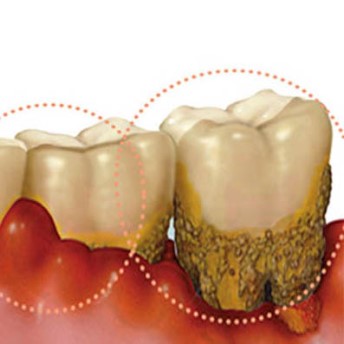

Răng số 8 mọc tương đối thẳng nhưng kẽ răng số 8 hở dẫn tới thức ăn bị giắt, gây hôi miệng, viêm lợi, viêm quanh răng.

Viêm lợi trùm: Do răng khôn mọc ra không hoàn toàn để loại 1 túi lợi phủ trên mặt răng khôn, túi lợi này là nơi lưu trữ thức ăn dẫn tới viêm lợi trùm và hôi miệng.